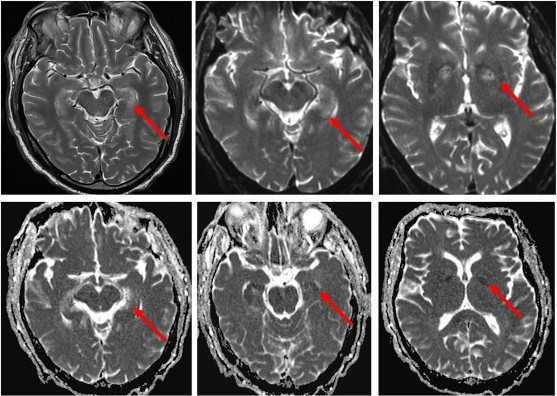

Tổn thương tái tưới máu đặc trưng bởi sự mất cân bằng trong cung cấp và sử dụng oxy sau hồi sinh tim phổi, dẫn tới chết tế bào não, xảy ra ngay sau khi tim đập lại. Các cấu trúc thần kinh nhạy cảm nhất bao gồm: hồi hải mã, đồi thị, vỏ não, thể chai và thùy nhộng tiểu não do là những mô có chuyển hóa nhiều (hình 1.2) [22],[26].

Hình 1.2. Hình ảnh cộng hưởng từ tổn thương não do thiếu oxy ở hồi hải mã và nhân xám hai bên [26].